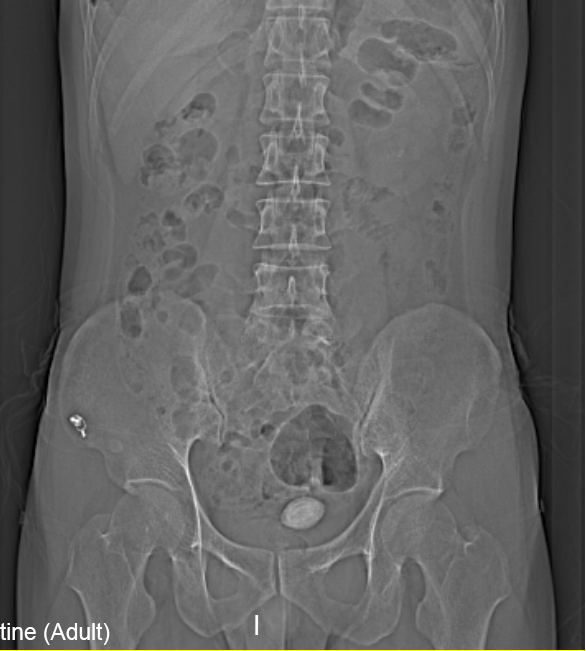

“醫(yī)生我尿不出,尿里有血,快幫幫我”。近日,在溫州市人民醫(yī)院泌尿外科門診一位男青年向坐診的黃來劍主任求助,經(jīng)驗豐富的黃主任在了解基本病情后,特意觸摸了一下患者恥骨上區(qū),并囑咐患者進(jìn)行泌尿系平片檢查,結(jié)果在意料之中也出乎意料之外。意料之中的是患者診斷如黃主任所想膀胱結(jié)石進(jìn)入尿道卡住了,意料之外的是結(jié)石直徑達(dá)到了35mm,像蛋黃大小了,這對年輕患者來說并不常見,堵住了尿道,把患者痛的夠嗆。

▲患者影像學(xué)檢查